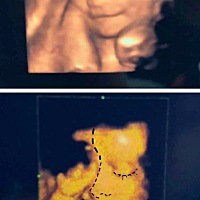

会是乌龙么……好紧张